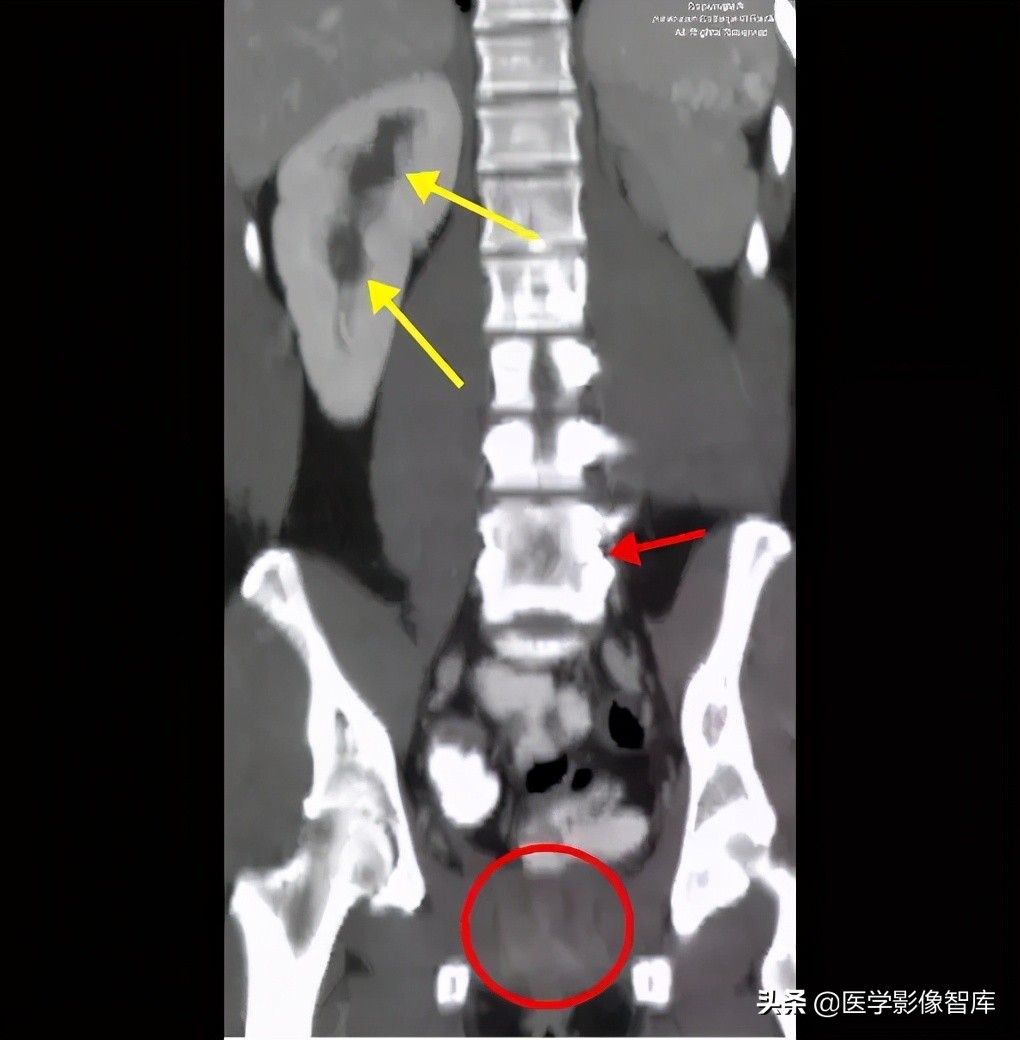

图 1. 冠状位 CT 显示左肾发育不全,右肾体积增大,集合系统扩张(黄色箭头),椎体融合(红色箭头),子宫及阴道缺如(红色圆圈)。